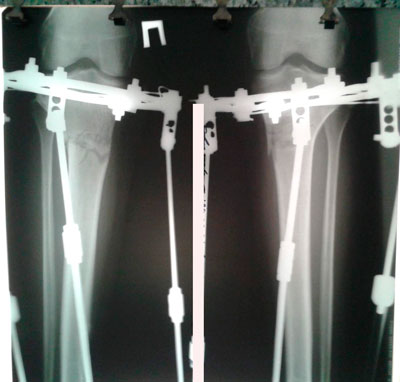

Дата операции 06.05.2016г.

Исходник - 32 года.

рентген до операции